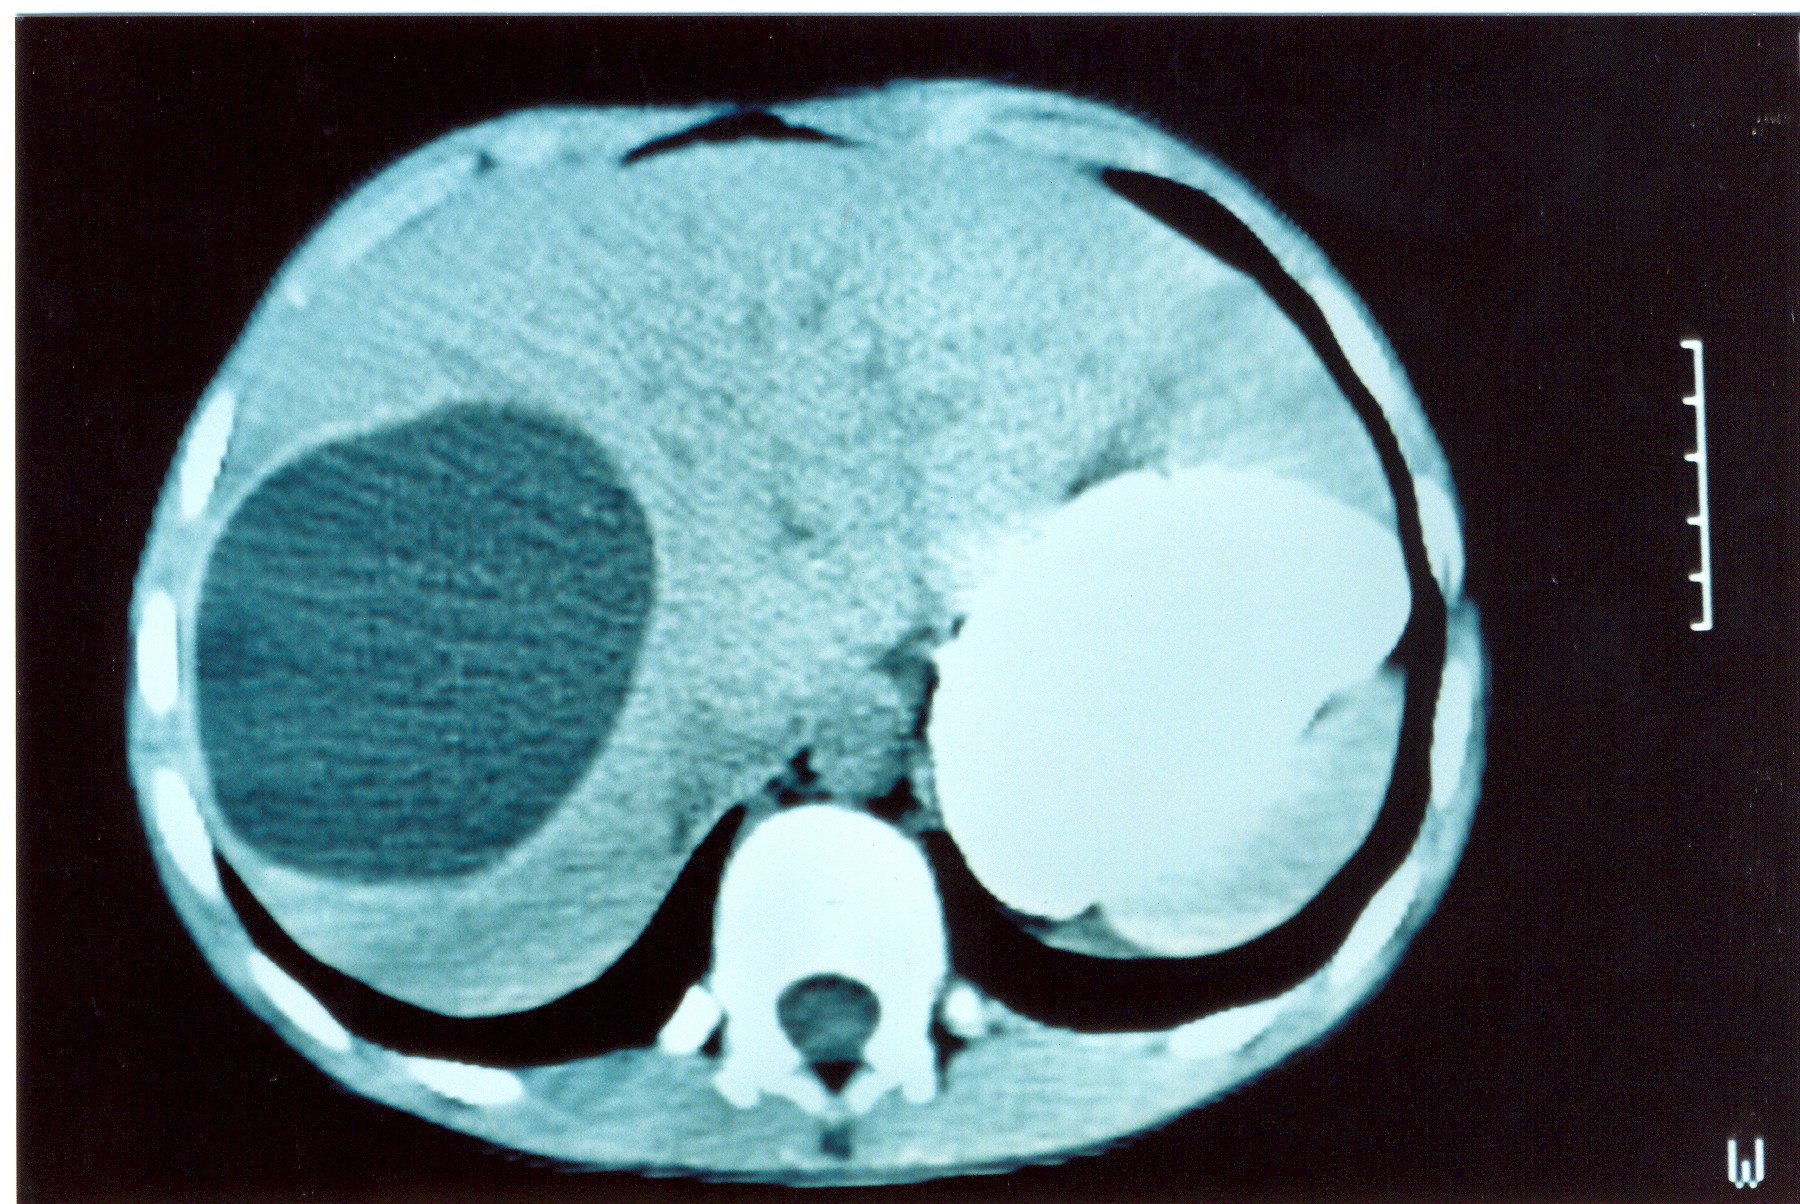

Large metastatic hepatic lesion, involving segments V, VI, VII, and part of VIII, 4.5 years after abdominoperineal resection of the rectum for poorly differentiated adenocarcinoma (Courtesy Dr. V. Penopoulos)